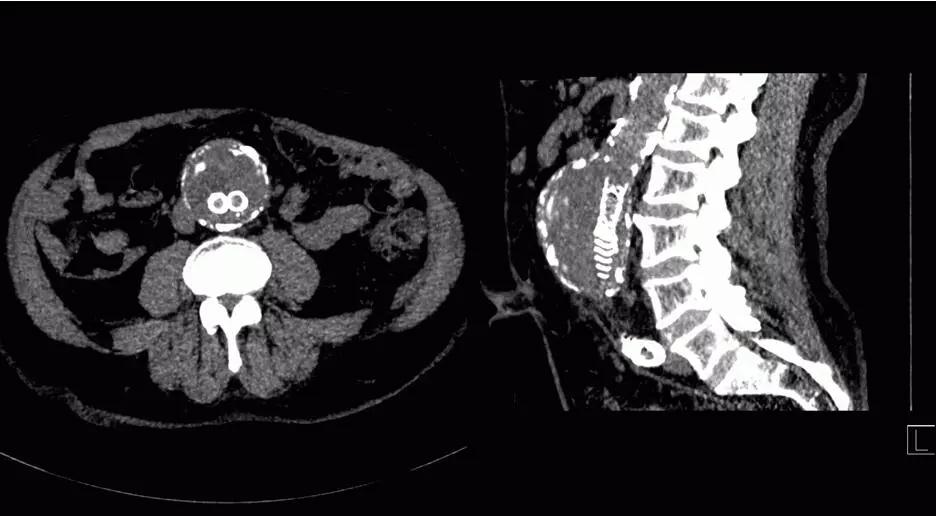

8. 類DSA成像:

傳統(tǒng)DSA成像有創(chuàng)而且操作復(fù)雜、掃描范圍受限。

SOMATOM Force 突破技術(shù)界限,將血流評估覆蓋范圍擴大至80cm,特別適合大范圍下肢血管疾病診斷,一次掃描一次注射即可無創(chuàng)精確判斷病變,更加精確地制定臨床決策,選擇合理的治療方法。

△80厘米無創(chuàng)CT DSA,影像決策診療